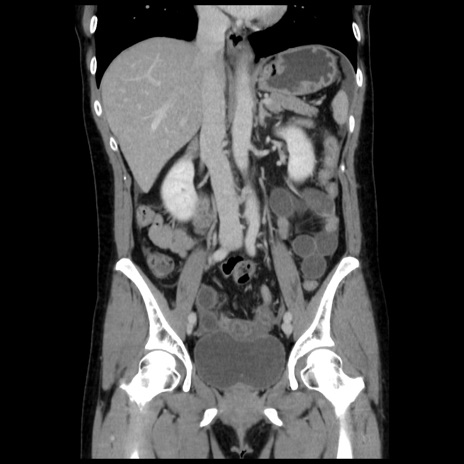

症例10(冠状断像)

【症例】 50歳代女性

【主訴】 腹痛

【現病歴】前日生レバーを食べた。今朝に排便あり。 昼前に突然発症の腹痛を生じ、当院救急外来を受診した。

【既往歴】 子宮筋腫にてで子宮全摘後

【身体所見】 意識清明、腹部:平坦、軟、下腹部やや左を中心に圧痛・反跳痛あり、筋性防御あり

【データ】WBC 7800、CRP 0.07